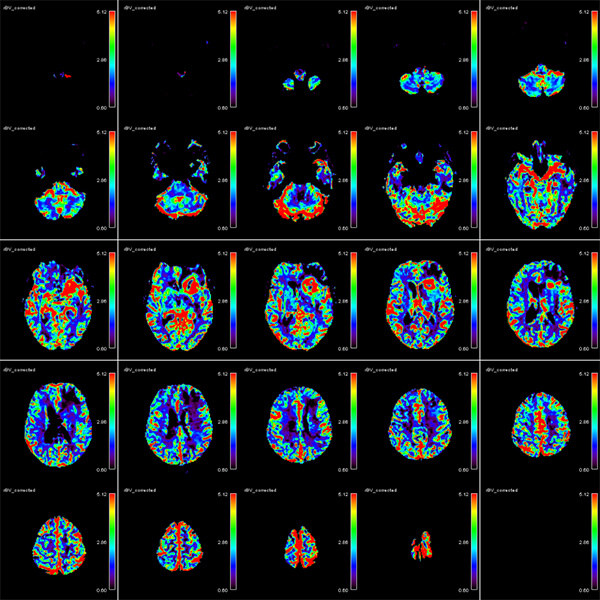

- Perfusion (techniques: DSC, DCE, ASL)